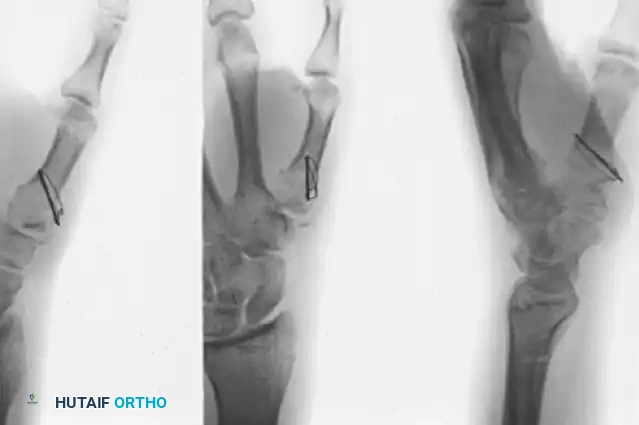

Surgical Technique: The Foster and Hastings Plating Method

Once exposure is achieved, the focus shifts to anatomic articular reduction and rigid internal fixation using a 2.7-mm system.

1. Fracture Reduction and Provisional Fixation

• Clear the fracture site of organized hematoma and interposed periosteum.

• Reduce the two large basilar fragments (the palmar and dorsal articular fragments). This is often achieved using a combination of longitudinal traction, pronation, and direct manipulation with a dental pick or small pointed reduction forceps.

• Provisionally fix the reduced articular fragments with a 0.035-inch or 0.045-inch Kirschner wire (K-wire). Verify the articular congruity under direct vision and fluoroscopy.

2. Plate Selection and Positioning

• Select a small T-plate or L-plate designed to accept 2.7-mm screws. The plate must be contoured to match the normal slight volar concavity of the thumb metacarpal.

• Place the transverse portion of the T-plate over the basilar fragments of the metacarpal.

• The K-Wire Slide Technique: The previously placed provisional K-wire should ideally slide through one of the two proximal holes in the transverse portion of the plate. If the alignment is incorrect, place a second K-wire in line with one of the plate holes, secure the fragments, and remove the first wire.

3. Articular Reconstruction with Interfragmentary Compression

To achieve absolute stability at the articular surface, the screws placed through the transverse portion of the plate must function as lag screws.

• Drilling the Thread Hole: With a 2.0-mm drill bit, drill through the free hole in the transverse portion of the plate, passing through both the near (dorsal) and far (palmar) articular fragments.

• Tapping: Tap the drilled hole with a 2.7-mm tap to prepare the thread profile.

• Overdrilling for Lag Effect: To achieve interfragmentary compression, the near cortex (the dorsal fragment) must be overdrilled to create a gliding hole. Use a 2.7-mm drill bit to overdrill only the dorsal fragment.

• Screw Insertion: Insert a 2.7-mm cortical screw of appropriate length. As the screw head engages the plate, it will compress the palmar articular fragment against the dorsal articular fragment.

• Second Proximal Screw: Repeat the exact same lag screw technique with the second proximal plate hole to secure the articular block.

4. Metacarpal Shaft Fixation

• Once the articular block is anatomically reconstructed and compressed, reduce the metacarpal shaft to the stabilized intra-articular fragments.

• Ensure rotational alignment is correct by assessing the thumb nail cascade relative to the index finger.

• Attach the diaphyseal portion of the metacarpal to the long longitudinal portion of the T-plate or L-plate using standard 2.7-mm cortical screws.